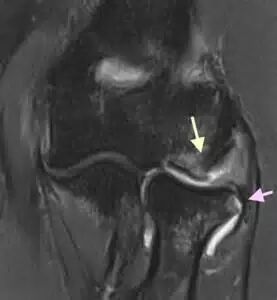

2 年后的 X 线片

2 年后 MRI 未发现桡骨头坏死